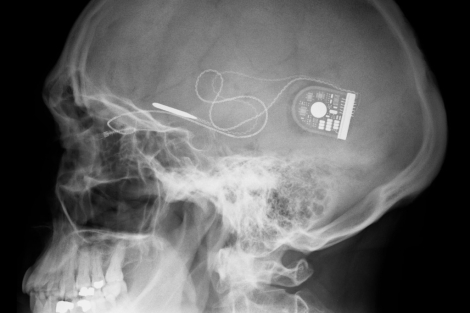

‘Retinas’ electrónicas contra la ceguera

Médicos del Reino Unido han probado con éxito la eficacia de un implante electrónico para las personas con un tipo de ceguera. Se trata de un ensayo clínico que pretende probar unaLeer más…